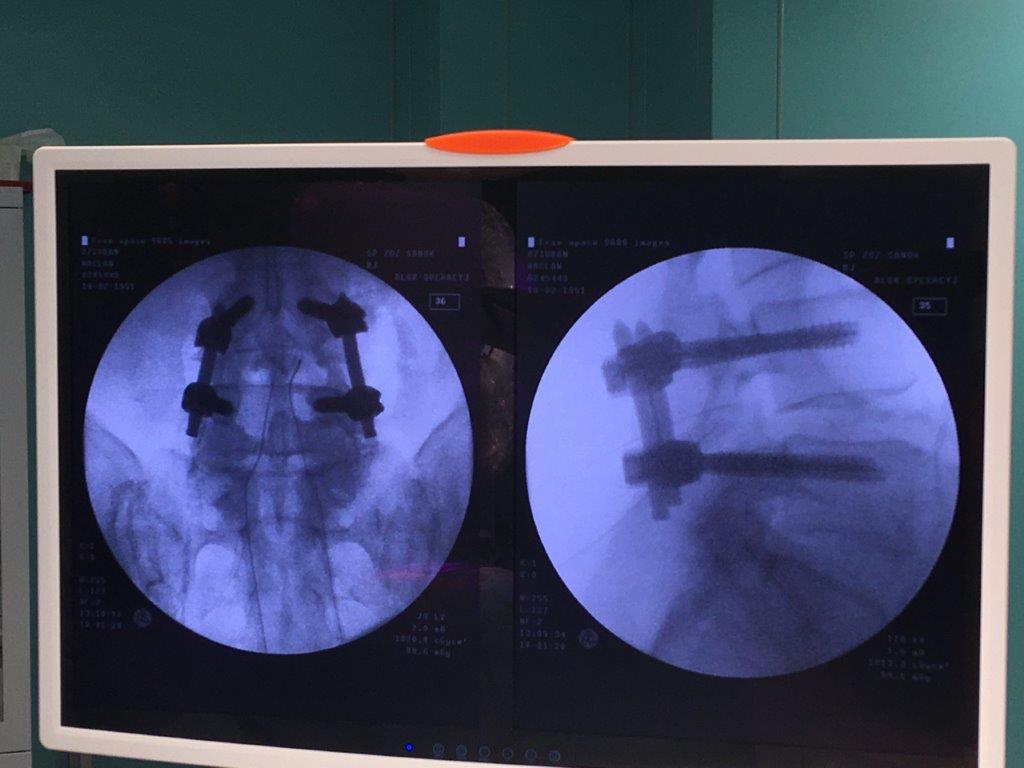

OPERACJA STENOZY KRĘGOSŁUPA LĘDŹWIOWEGO TECHNIKĄ MINIMALNIE INWAZYJNĄ Z ZASTOSOWANIEM NOWOCZESNYCH IMPLANTÓW WPROWADZONYCH PRZEZSKÓRNIE.

Uruchomienie nowego Bloku Operacyjnego pozwala na poszerzanie spektrum procedur zabiegowych dla pacjentów Specjalistycznego Szpitala w Sanoku. Dnia 10.01.2020 w Szpitalu w Sanoku neurochirurdzy Robert Konior i Marcin Czternastek wykonali zabieg operacyjny u pacjenta ze stenozą kanału kręgowego w odcinku lędźwiowym techniką minimalnie inwazyjną. Lekarze w pierwszej kolejności mikrochirurgicznie odbarczyli struktury nerwowe kanału kręgowego

a następnie dokonali przezskórnej stabilizacji kręgosłupa nowoczesnymi tytanowymi implantami. Operacja przebiegła bez powikłań a pacjent czwartego dnia opuścił szpital będąc samodzielny. Powyższa technika umożliwia uruchamianie pacjenta już następnego dnia po operacji i szybki powrót do sprawności ( dwukrotnie szybszy niż w przypadku technik klasycznych).